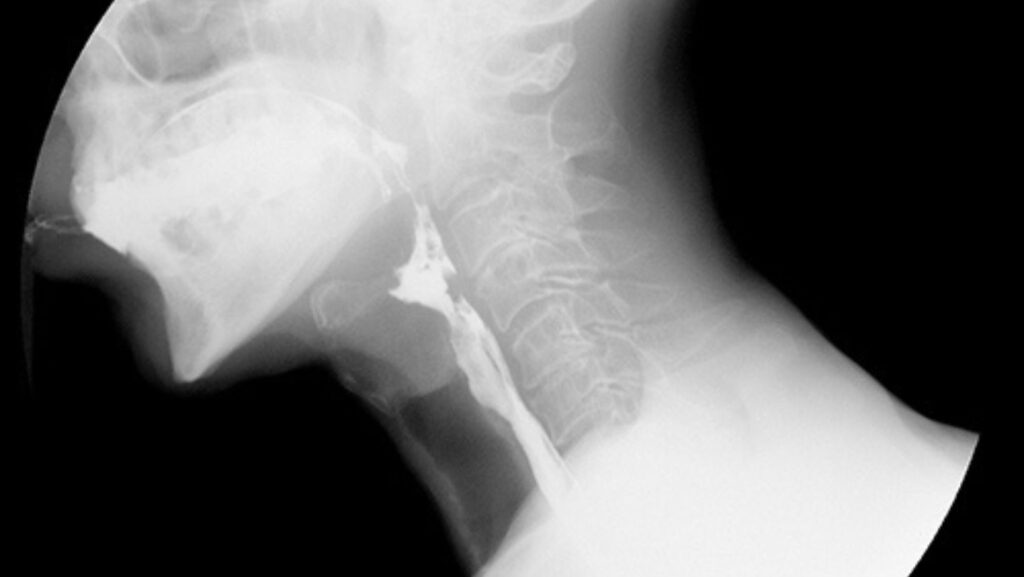

L’Rx Laringe è una tecnica radiologica che consente di ottenere immagini dettagliate della laringe e delle sue componenti principali, come le corde vocali e la glottide. Questo esame permette agli specialisti del Poliambulatorio S-Medical Group di Sora di esaminare con precisione eventuali anomalie strutturali o funzionali, rendendolo indispensabile per chi presenta disturbi vocali, difficoltà respiratorie o sintomi persistenti legati alla deglutizione.

L’Rx Laringe prevede l’ingestione di una piccola quantità di mezzo di contrasto da parte del paziente, che consente di evidenziare al meglio le strutture della laringe durante l’esame. Successivamente, vengono acquisite diverse immagini mentre il paziente compie azioni vocali specifiche, come la pronuncia di determinati suoni. Questo consente agli specialisti di osservare il comportamento dinamico delle corde vocali e di identificare eventuali disfunzioni o lesioni presenti.